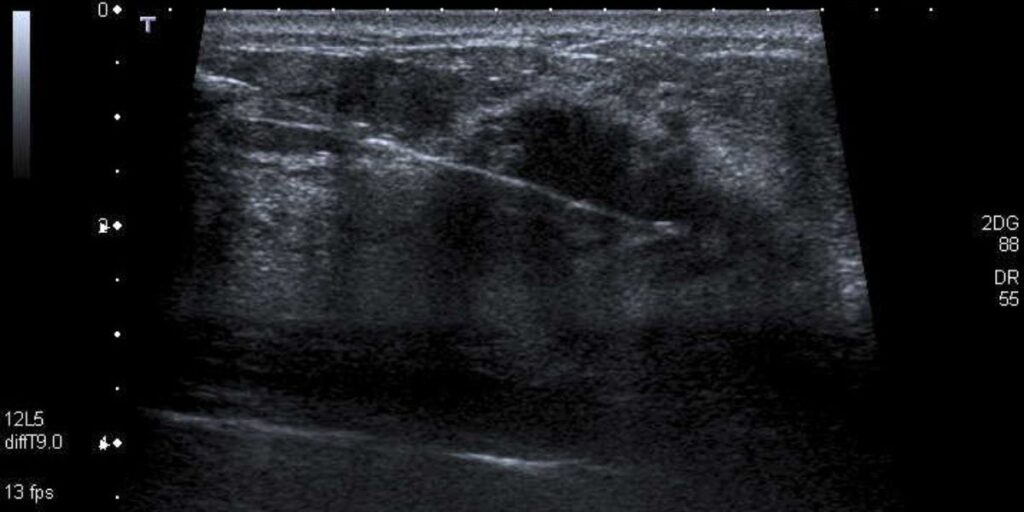

Durante la procedura, il paziente viene posizionato in modo da facilitare l’accesso alla zona da esaminare. Il medico utilizza tecniche di imaging come l’ecografia o la tomografia per guidare l’ago Tru-Cut nel punto preciso. Una volta individuata la posizione corretta, l’ago viene inserito nel tessuto per prelevare il campione. Questo tessuto viene poi inviato al laboratorio per essere analizzato al microscopio, consentendo una valutazione accurata della sua natura.

Presso il Poliambulatorio S-Medical Group di Sora, l’esame viene eseguito in modo professionale e attento al comfort del paziente. Prima della procedura, il medico spiega i dettagli dell’esame e risponde a eventuali domande. Il paziente viene preparato con anestesia locale per ridurre qualsiasi fastidio. Durante la biopsia, l’ago Tru-Cut viene inserito sotto guida ecografica per prelevare il campione di tessuto necessario. Alla fine, il paziente sarà monitorato per breve tempo prima di essere dimesso.